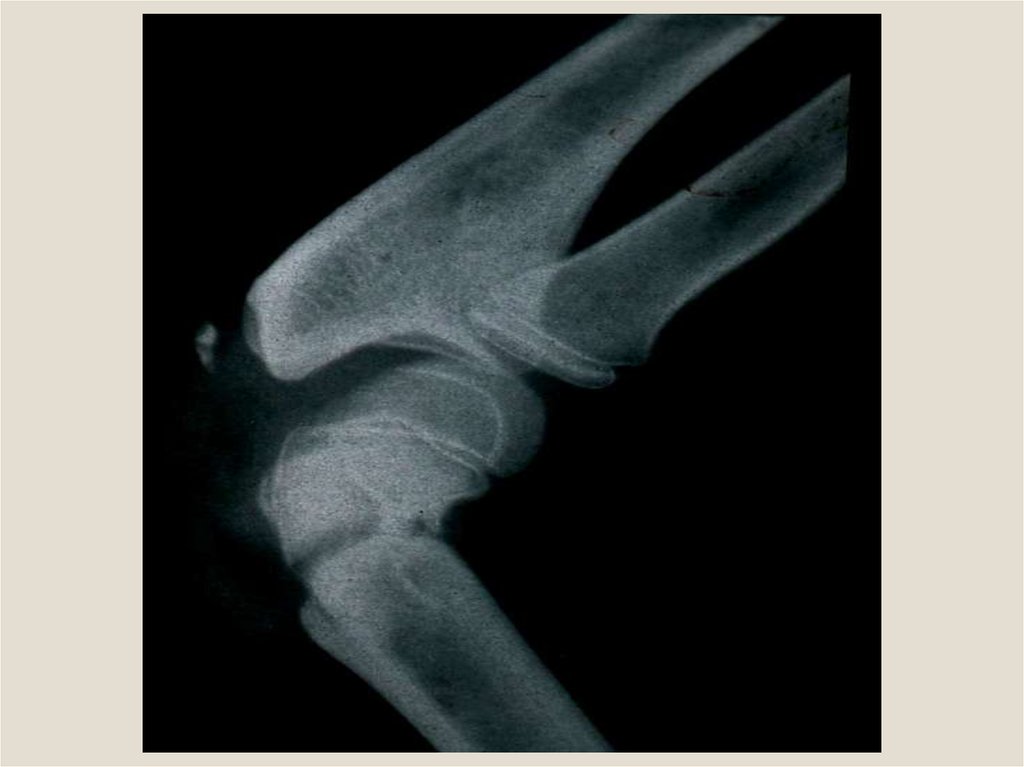

Клиническая анатомия смещения отломков при переломах трубчатых костей. Остеотомия, остеосинтез, пластика трубчатых костей